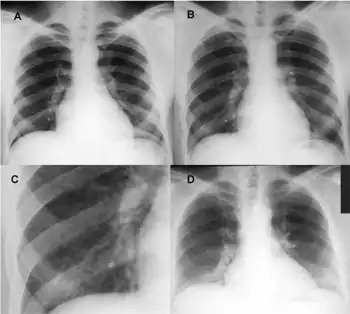

a)Normal b) episode of acute work-related illness -nodular infiltrate c) close-up d)reduced lung volumes

The diagnosis for this condition is based on the following:[7]

• Chest X-ray